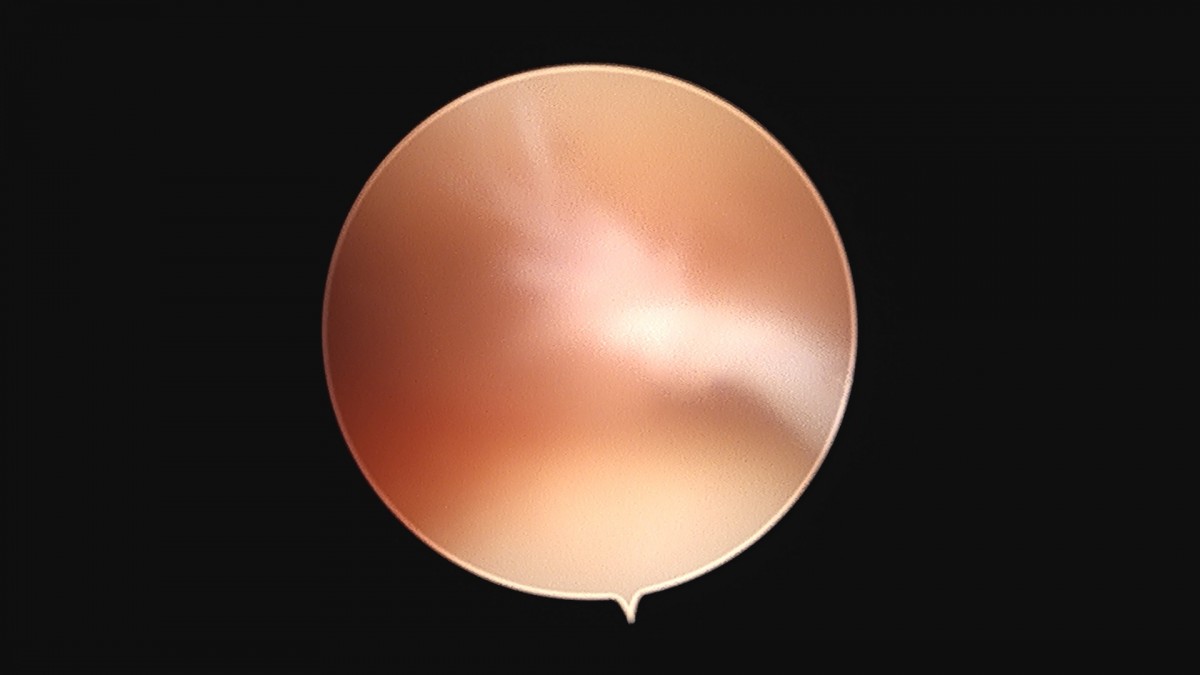

이재상원장님 무릎 변연절제술 권오O 환자

작성자 최고관리자 댓글 0건 조회 373회 작성일 25-09-16 16:11